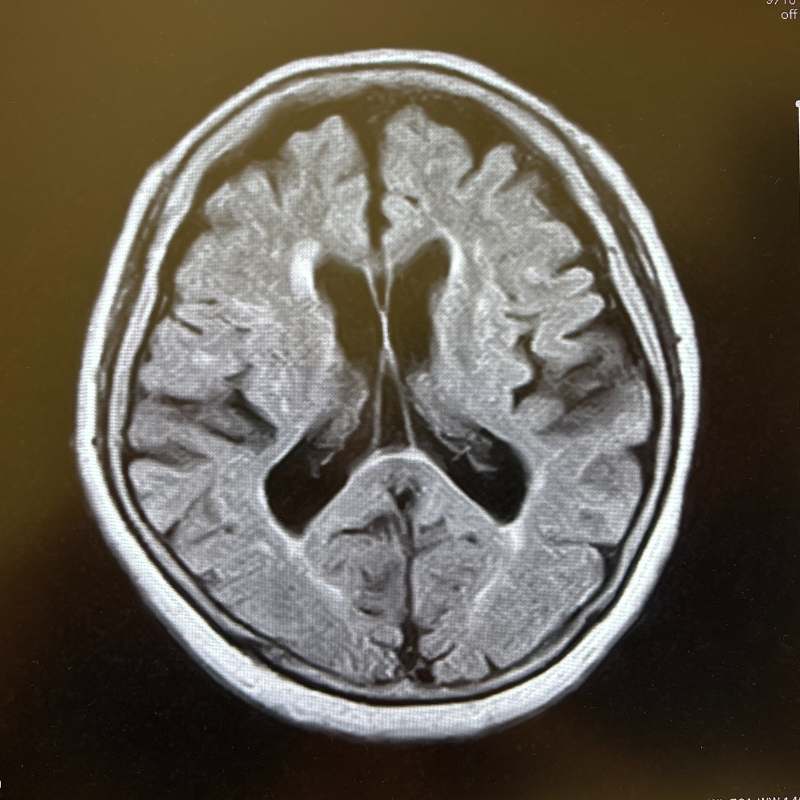

MRI画像例

下の画像は、当院で行うMRI・MRA検査で撮影できる脳の写真の一例です。

MRIでは脳の形や組織の状態を、MRAでは脳の血管の様子を詳しく確認できます。

2D画像